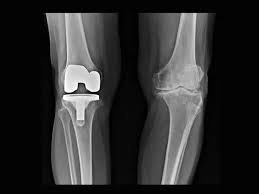

Knee Replacement surgery Cost In Pune

Knee replacement surgery cost in Pune varies because no two patients share identical joint damage, activity demands, or recovery requirements. Generally, costs differ based on whether the surgery involves a single knee or both knees, partial versus total replacement, and standard versus advanced implant options. Additionally, hospital stay duration and rehabilitation needs also influence the final amount.

Several factors directly impact knee replacement surgery cost. First, implant selection plays a major role, as implant design, durability expectations, and biomechanical suitability vary between patients. Second, surgical complexity affects cost, particularly in cases involving severe deformity, stiffness, or previous surgeries.

Surgical Technique, Implant Choice, and Cost Balance

Modern knee replacement surgery emphasizes precision, alignment accuracy, and long-term implant performance. However, advanced techniques and high-quality implants can influence overall cost. The key lies in balancing clinical benefit with affordability rather than choosing options blindly.

Dr. Aniruddha Deshmukh guides patients through implant selection by explaining durability expectations, activity compatibility, and long-term joint function. As a result, patients invest in solutions that match their lifestyle rather than overpaying for unnecessary features.